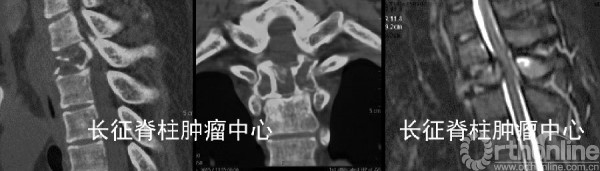

第一次術前CT、MRI均提示胸2椎體溶骨性破壞。

當地醫院行后路胸2椎體次全切除取髂骨植骨重建內固定術,術后5月,X線,CT及MRI均提示胸1-3椎體溶骨性破壞,考慮胸2腫瘤組織殘留、復發并侵及鄰近椎節。